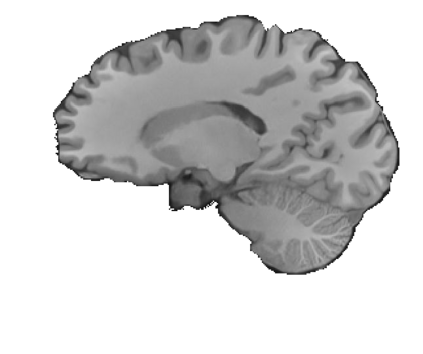

Magnetic resonance (MR) images are often acquired in 2D settings for real clinical applications. The 3D volumes reconstructed by stacking multiple 2D slices have large inter-slice spacing, resulting in lower inter-slice resolution than intra-slice resolution. Super-resolution is a powerful tool to reduce the inter-slice spacing of 3D images to facilitate subsequent visualization and computation tasks. However, most existing works train the super-resolution network at a fixed ratio, which is inconvenient in clinical scenes due to the heterogeneous parameters in MR scanning. In this paper, we propose a single super-resolution network to reduce the inter-slice spacing of MR images at an arbitrarily adjustable ratio. Specifically, we view the input image as a continuous implicit function of coordinates. The intermediate slices of different spacing ratios could be constructed according to the implicit representation up-sampled in the continuous domain. We particularly propose a novel local-aware spatial attention mechanism and long-range residual learning to boost the quality of the output image. The experimental results demonstrate the superiority of our proposed method, even compared to the models trained at a fixed ratio.

翻译:磁共振图像通常在 2D 环境中获得,用于真正的临床应用。通过堆叠多个 2D 切片重建的 3D 体积具有很大的切片间距,导致切片间分辨率低于切片分辨率。超级分辨率是减少3D 图像间隔的有力工具,以便利随后的可视化和计算任务。然而,大多数现有工程都以固定比例对超级分辨率网络进行培训,这在临床场景中不方便,因为MR 扫描的参数各异。在本文中,我们提议建立一个单一的超级分辨率网络,以任意调整比例降低MR 图像的切片间间间距。具体地说,我们将输入图像视为坐标的一个连续的隐含功能。不同间距比率的中间切片可以按照连续域内隐含的显示比例来构造。我们特别提议了一个新的地方觉空间关注机制和远程留置学习,以提高输出图像的质量。实验结果显示我们拟议方法的优越性,即使与所培训的模型相比,也是一种固定比例。